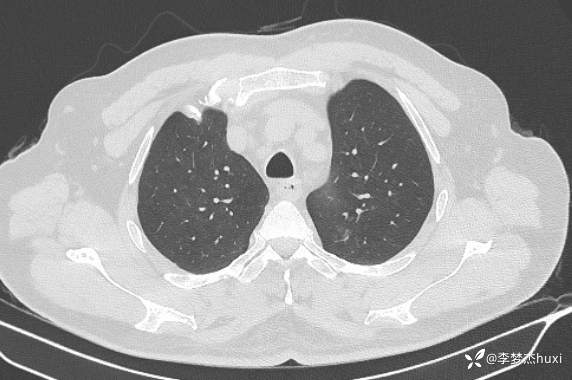

男性48岁,咯血3小时,咯血病因?

主诉:咯血3小时

简要病史:患者于入院前3小时无明显诱因出现咯血,为鲜红色,量较多,约10ml,伴胸闷、压气,伴咳嗽,无明显咳痰。

体格检查:T36.2℃,P110次/分,R20次/分,BP250/130mmHg。神清,呼吸平稳,浅表淋巴结不大,双肺叩清音,双肺未闻及干湿性啰音,心率110次/分,律齐,无杂音。腹部平坦,软,全腹无压痛,无反跳痛及肌紧张,肝脾肋下未触及,双下肢无水肿。

辅助检查:胸部CT:双肺炎症,双肺纹理增多,主动脉及冠状动脉钙化,主肺动脉稍增粗,右侧肾上腺点状高密度影,考虑脂肪肝。

临床诊断:肺炎咯血